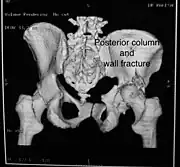

Posterior column and wall fracture as seen on 3D CT

| Posterior column | As with posterior wall injury, this also typically occurs due to dash board injury. | Posterior column + Posterior wall | These fractures are extensions of elementary fractures. With the involvement of the posterior wall, the difficulty in treatment increases. These fractures are rarely amenable to non-surgical treatment. Due to posterior wall fracture, the hip is usually dislocated posteriorly, requiring immediate reduction of dislocation and surgical reconstruction after a few days.

The posterior column with posterior wall fracture occurs due to dashboard injury. The anteroposterior view may give clues to these injuries. Judet views and CT scans help in knowing the extent of the injury. |